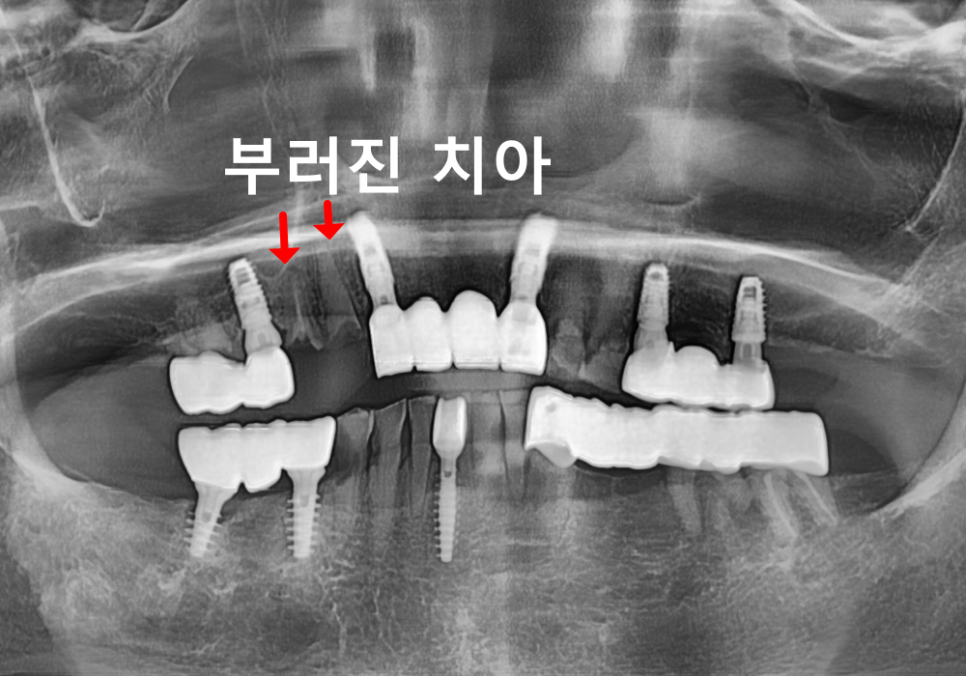

확인해 보니

이전에 말씀드린 앞니 쪽이 문제였죠.

240404

1년 전보다 상태가 더

진행돼 있었는데요.

충치가 오래 누적되면서

치아는 사실상 뿌리만 남은 상태였고,

치아 뿌리도 흡수가 진행돼

짧아져 있었습니다.

이런 경우는 기둥을 넣어

보철을 새로 만들더라도

오래 쓰지 못할 가능성이 높습니다.

그래서

앞니 3개를 발치한 뒤

임플란트로 회복하기로 했습니다.